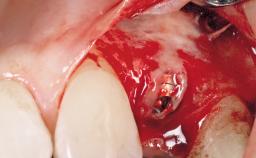

Surgical treatment of a 68-year-old female patient with a distal extension situation in the left mandible. As the CBCT analysis reveals, the bone crest anatomy in the area is not ideal and necessitates an augmentation procedure to achieve a good long-term prognosis for the planned implants and their prostheses.

After the placement of three diameter-reduced two-piece implants the bone is augmented with autologous bone chips and DBBM particles to enlarge the crest volume. The surgery is completed with the application of two membrane layers and primary wound closure.

For soft tissue management, the initial healing caps are replaced with a longer type 8 weeks after implant placement in a second intervention before prosthodontic treatment is initiated.